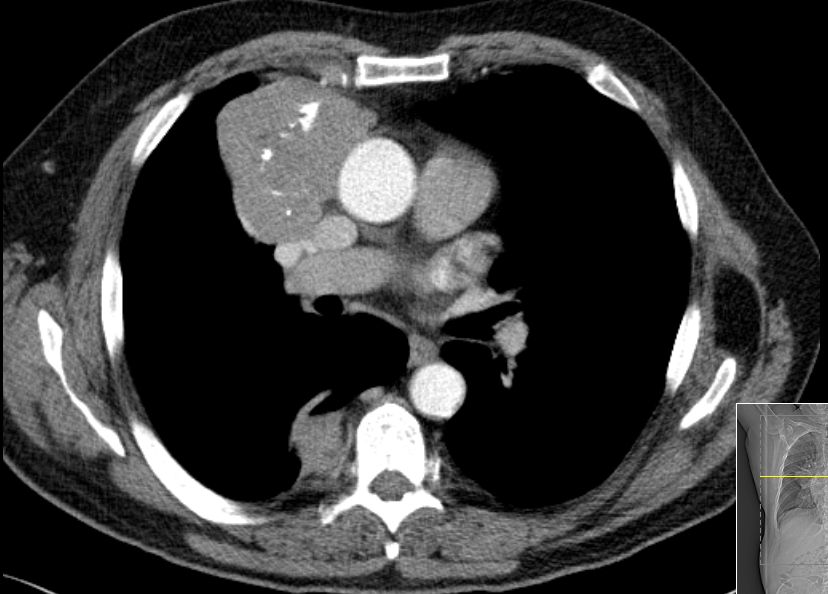

| B3-Thymom | 52-jährige adipöse Frau ohne Myasteniesymptome mit rezidivierenden Bronchopneumonien.

Histologisch ergab sich ein B3-Thymom mit Infiltration des Fettgewebes. |